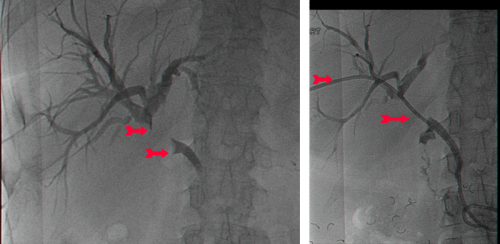

שיטה נוספת לניקוז דרכי המרה תוארה בראשונה ב- 1980. בשיטה זו דרכי המרה החסומות מנוקזות בעזרת תותב שהוחדר ישירות דרך פטמת ווטר (Vater) לתוך צינור המרה המשותף. החדרת התותב בוצעה בעזרת אנדוסקופ במהלך ERCP (תצלום 53.8). הפעולה מצליחה ב- 90% מהמקרים, ושכיחות התחלואה היא 10%. התמותה המדווחת בעקבות פעולה זו היא בשיעור 2%, והתמותה הסב-פעולתית (בתוך 30 יום) היא בשיעור של כ- 10%. הסיבוך השכיח ביותר הוא דלקת עולה בדרכי המרה (8%). סיבוך שכיח נוסף הוא חסימת התותב וצהבת חסימתית גוברת.

פעולות להקלה יכולות להתבצע גם דרך ה- PTC (Percutaneous transhepatic cholangiogram). לאחר הדגמת דרכי המרה מחדירים צינורית קשיחה שבה נקבים רבים, ובשיטה מיוחדת, בהנחיית שיקוף, חודרים את השאת החוסמת ומעבירים חלק מהצינור מעבר לחסימה, כך שהמרה יכולה לזרום דרך נקבים אלה לתוך התריסריון. שיטה זו חוסכת ניתוח בשלביה המתקדמים של המחלה.